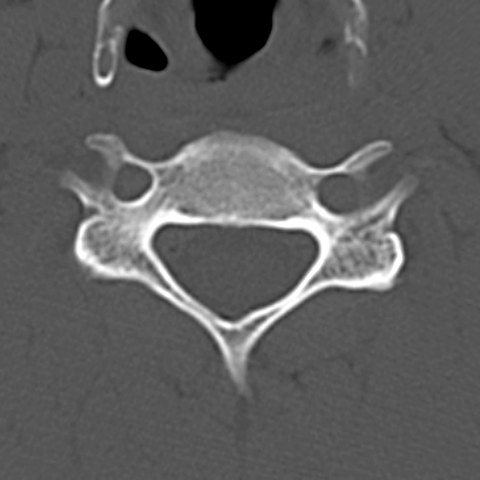

Cervical Spine, C5 level [8 of 8]